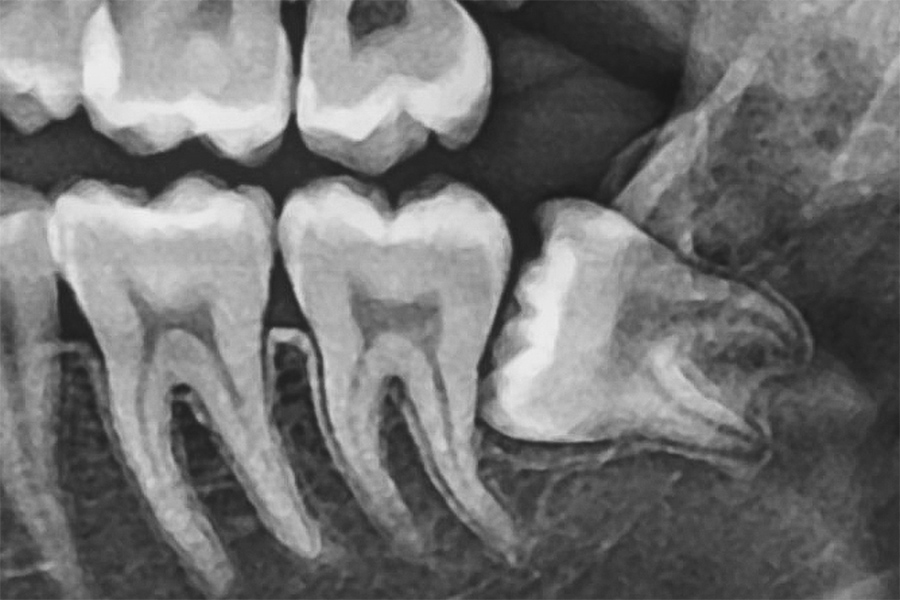

パノラマレントゲン

パノラマレントゲンは、お口全体を1枚の画像で撮影できる広範囲のレントゲン写真です。親知らずの位置や向き、周囲の歯との関係を一目で確認できます。

特に下あごの親知らずは、下歯槽神経という重要な神経の近くにあることが多いです。抜歯にあたっては、神経との距離や重なり具合を事前に把握し、神経損傷のリスクを回避することが重要です。